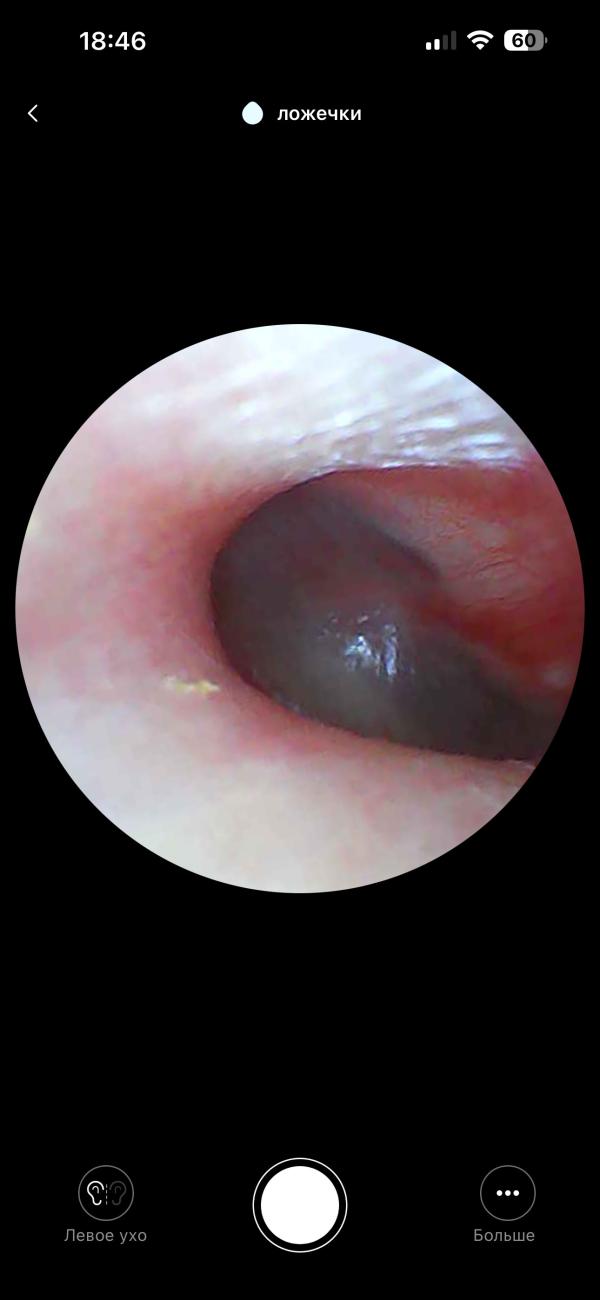

post image 2

Кто знает, это отит?(((( подскажите плиз 😢

У нас такое было , врач показывал на экране , был отит 2 степени

Я не врач, но я тоже так смотрю. Перепонка не повреждена, а снаружи краснота, значит отипакс лишним не будет и не навредит

@bakaeva_krg да, когда такая картина у сына, врач обычно пишет наружный средний отит